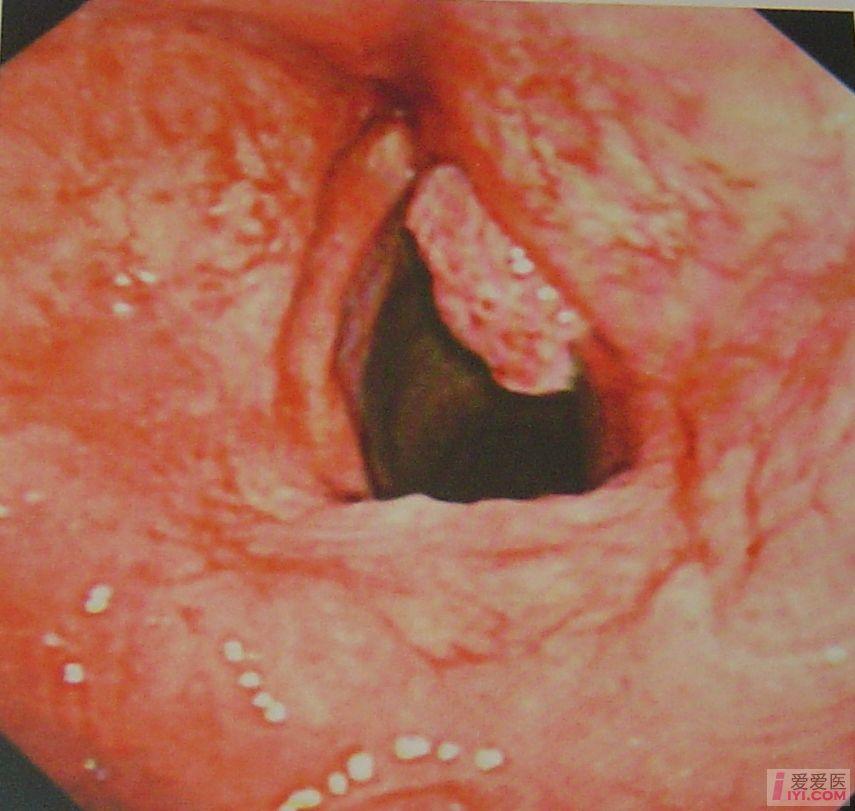

喉癌一临床表现与诊断

喉癌(一)临床表现与诊断